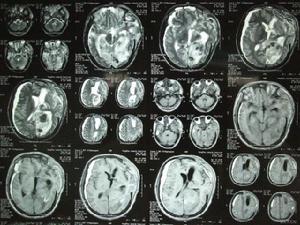

2.頭顱B超和CT檢查除外顱內出血